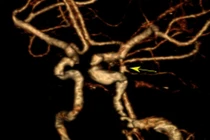

Túi phình mạch não là tình trạng thành động mạch não bị yếu và phồng lên tạo thành một túi nhỏ. Khi túi phình lớn dần, thành mạch trở nên mỏng và dễ vỡ.

Túi phình mạch máu não là tình trạng mạch máu trong não bị phình ra tại một ví trí nào đó. Khi bị vỡ, người bệnh phải đối mặt với những hậu quả nghiêm trọng đến tính mạng như đột quỵ xuất huyết não, động kinh...

Phình mạch máu não là căn bệnh tiềm tàng nguy hiểm, nếu không được phát hiện và điều trị, khi vỡ sẽ rất nguy hiểm, để lại nhiều biến chứng nặng nề, thậm chí là tử vong.